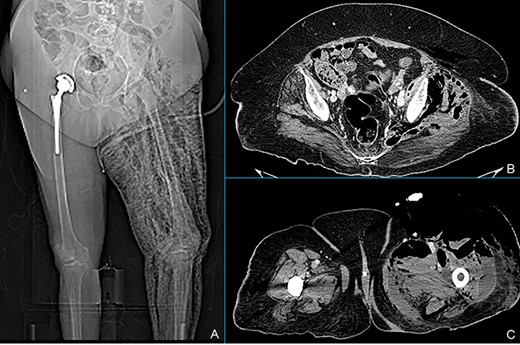

Total body X-ray shows marked left leg emphysema (A). CT scan of the lower abdomen showing covered posterior sigmoid perforation, sigmoid thickening and retroperitoneal collections (B). Marked air and fluid collections in medial and anterolateral compartment of the left leg at the CT scan (C).

We report a case of a 71-year-old woman with Class 3 obesity and Type 2 diabetes. The patient initially came to the emergency room for abdominal pain, fever (38.5°C) and swelling of the left lower limb. The blood tests showed a neutrophilic leukocytosis with white blood cells (WBC) 15 700 cells/mmc, neutrophils 13 800 cells/mmc, C-reactive protein (CRP) 303 mg/l and serum glucose 275 mg/dl. At the physical examination, the abdomen was soft with lower left quadrant tenderness, and the left lower limb was painful and warm with marked edema starting from the inguinal region. The patient was hemodynamically stable. Computed tomography (CT) scan of the abdomen extended to the lower limbs (Fig. 1) revealed the presence of air and fluid retroperitoneal collections, extending through the posterior abdominal wall muscles until the medial and anterolateral compartment of the left leg. Besides, thickening of the sigmoid wall with covered perforation was detected. Clinical and radiological findings were consistent with extensive gangrenous fasciitis possibly secondary to perforated diverticulitis. Wide-spectrum antibiotic therapy with meropenem and vancomycin was started and urgent fasciotomies were performed on the anterior, medial and lateral sides of the left leg. The patient was also treated with hyperbaric oxygen therapy and referred to the intensive care unit (ICU). A cultural test showed a polymicrobial infection of Klebsiella pneumoniae, Enterococcus faecalis and Candida albicans. Blood cultures were positives for Staphylococcus epidermidis. According to these findings, the antibiotic therapy was implemented by adding fluconazole and the hyperbaric therapy was stopped. The first postoperative course was uneventful. In postoperative Day (POD) 8, a CT scan showed a reduction of collections both in the retroperitoneum and in the left leg prompting the discharge of the patient from ICU. At that moment, we decided not to treat the diverticulitis surgically, according to the recent Consensus Statement of the European Association for Endoscopic Surgery and Society of American Gastrointestinal and Endoscopic Surgeons. In POD 16, since blood tests were completely normalized, physical examination of the abdomen was negative and surgical incisions were dry and clean, the patient was transferred to the rehabilitation unit. After 37 days from surgery, the patient was readmitted to our unit because of the occurrence of fever and the formation of a fistula at the site of the lateral fasciotomy producing fecal material (Fig. 2). The CT scan revealed marked improvement of abdominal and limb conditions, with a reduction of the pericolic abscess, collections and edema of the left leg (Fig. 3). Lab tests showed WBC 7800 cells/mmc, CRP 183 mg/l. Although CT scan findings showed improvement, the clinical evidence of colocutaneous fistula prompted us to surgery. Intraoperative findings confirmed acute diverticulitis with posterior covered perforation and retroperitoneal fistula. An enterocolic fistula was also detected. There was no contamination of the peritoneal cavity; so we performed sigmoid resection with primary mechanical end-to-end anastomoses without proximal diversion and ileal loop repair. Two drain tubes were placed both in the abdominal cavity and through the lateral fasciotomy. No early or late severe postoperative surgical complications were observed. In POD 4, the patient returned to normal bowel function and started oral refeeding. Abdominal and left leg drain tubes were respectively removed in PODs 5 and 7. An episode of fever (39.3°C) occurred in POD 9 and was attributed to candida infection and treated with antifungal therapy and central venous catheter removal. In POD 27, the patient was finally discharged in good clinical condition with normal lab tests and left leg wound re-epithelialization.